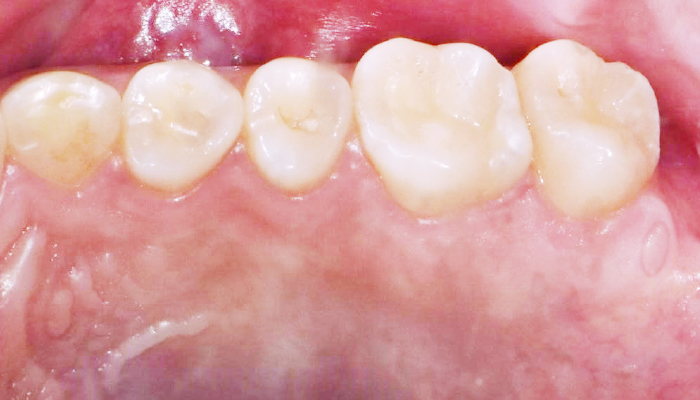

스케일링은 칫솔질로 제거되지 않은 치석과 치태를 제거하여 치석으로 인한 잇몸질환, 충치, 구취 등을 예방하는 치료입니다. 최근에 건강보험이 적용되어 1년에 한 번, 보험 혜택을 통해 스케일링을 받으실 수 있습니다.

거칠어진 치아 표면을 매끄럽게 해줍니다.

• 잇몸 건강 효과

잇몸 건강에 도움이 됩니다.